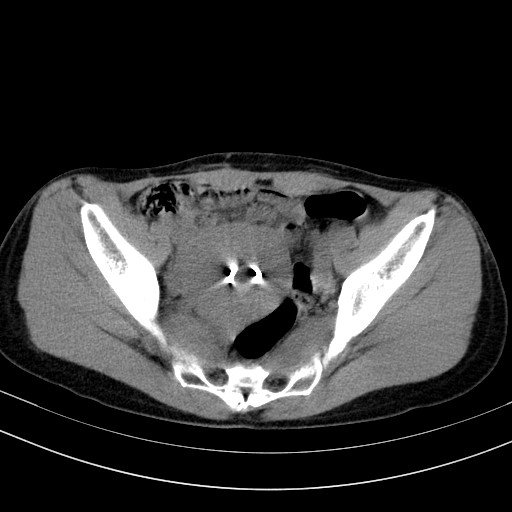

以下是引用随光逐影在2009-4-7 8:17:00的发言:[br]考虑宫颈占位性病变(宫颈癌?);建议行进一步检查。

以下是引用jiangjing在2009-4-7 16:46:00的发言:[br]宫颈增大,结构不清,右侧附件区可疑囊样占位,建议增强及mri 检查